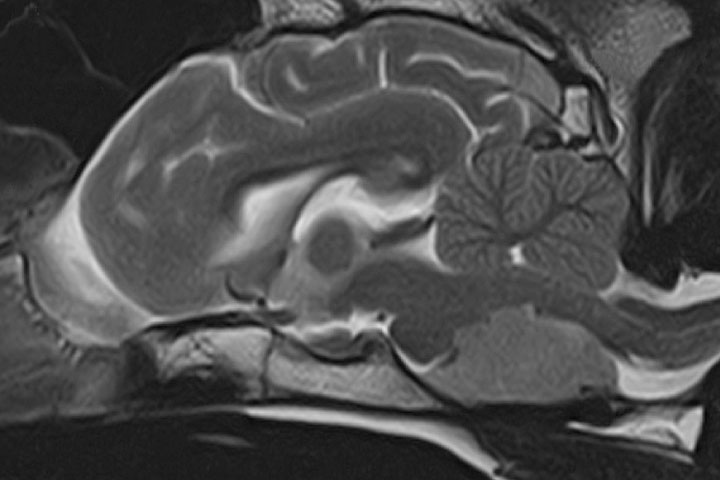

Pituitary masses

Pituitary adenomas or adenocarcinomas are the most common type of pituitary tumours. They can cause neurological signs by compressing the diencephalon. Clinical signs tend to be subtle and may only relate to hypothalamic dysfunction: low temperature, heart rate and decreased mentation. The oculomotor nerve (pupil size and eyeball movement) can be affected. On many occasions they cause hyperadrenocorticism.

On MRI or CT they appear as a single mass in the skull base-medial cranial fossa extending dorsally.